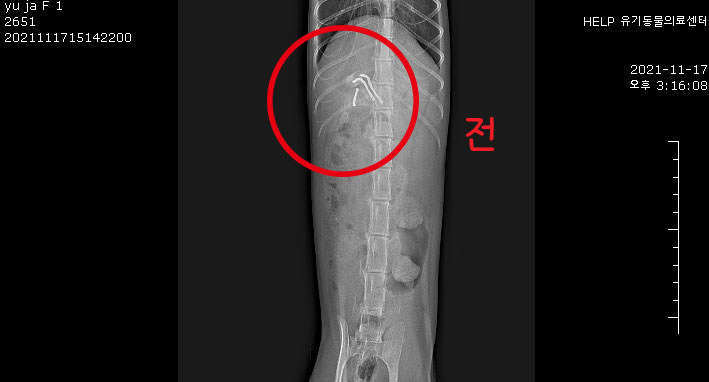

Áï½Ã Ÿ º´¿ø¿¡¼­ X-ray ÃÔ¿µÇß°í,

±Ý¼Ó ¹× ¾Ë ¼ö ¾ø´Â ³Îµû¶õ ÇüÅÂÀÇ ¹°Ã¼°¡ À§ ³»¿¡¼­ ¹ß°ßµÇ¾ú¾î.

¼ö¼ú Àü X-ray ÀçÃÔ¿µ Çߴµ¥, ¿©ÀüÈ÷ À§ ³»¿¡ ÀÖ´Â °ÍÀ¸·Î È®ÀεǾú¾î.

±Ý¼Ó ¹°Ã¼°¡ ±â´Ù¶þ°í »ÏÁ·Çϱ⠶§¹®¿¡ ³»½Ã°æÀ¸·Î´Â À§ ³»¿¡¼­ ²¨³»±â Èûµé °ÍÀ¸·Î »ý°¢µÇ¾î,

Áß¼ºÈ­¿Í µ¿½Ã¿¡ À§ Àý°³¸¦ ÇØ¼­ À̹°À» Á¦°ÅÇϱâ·Î Çß¾î.

¾à 0.3cm °¡·® À§ Àý°³ ÈÄ À̹°À» Á¶½É½º·´°Ô ²¨³Â¾î.